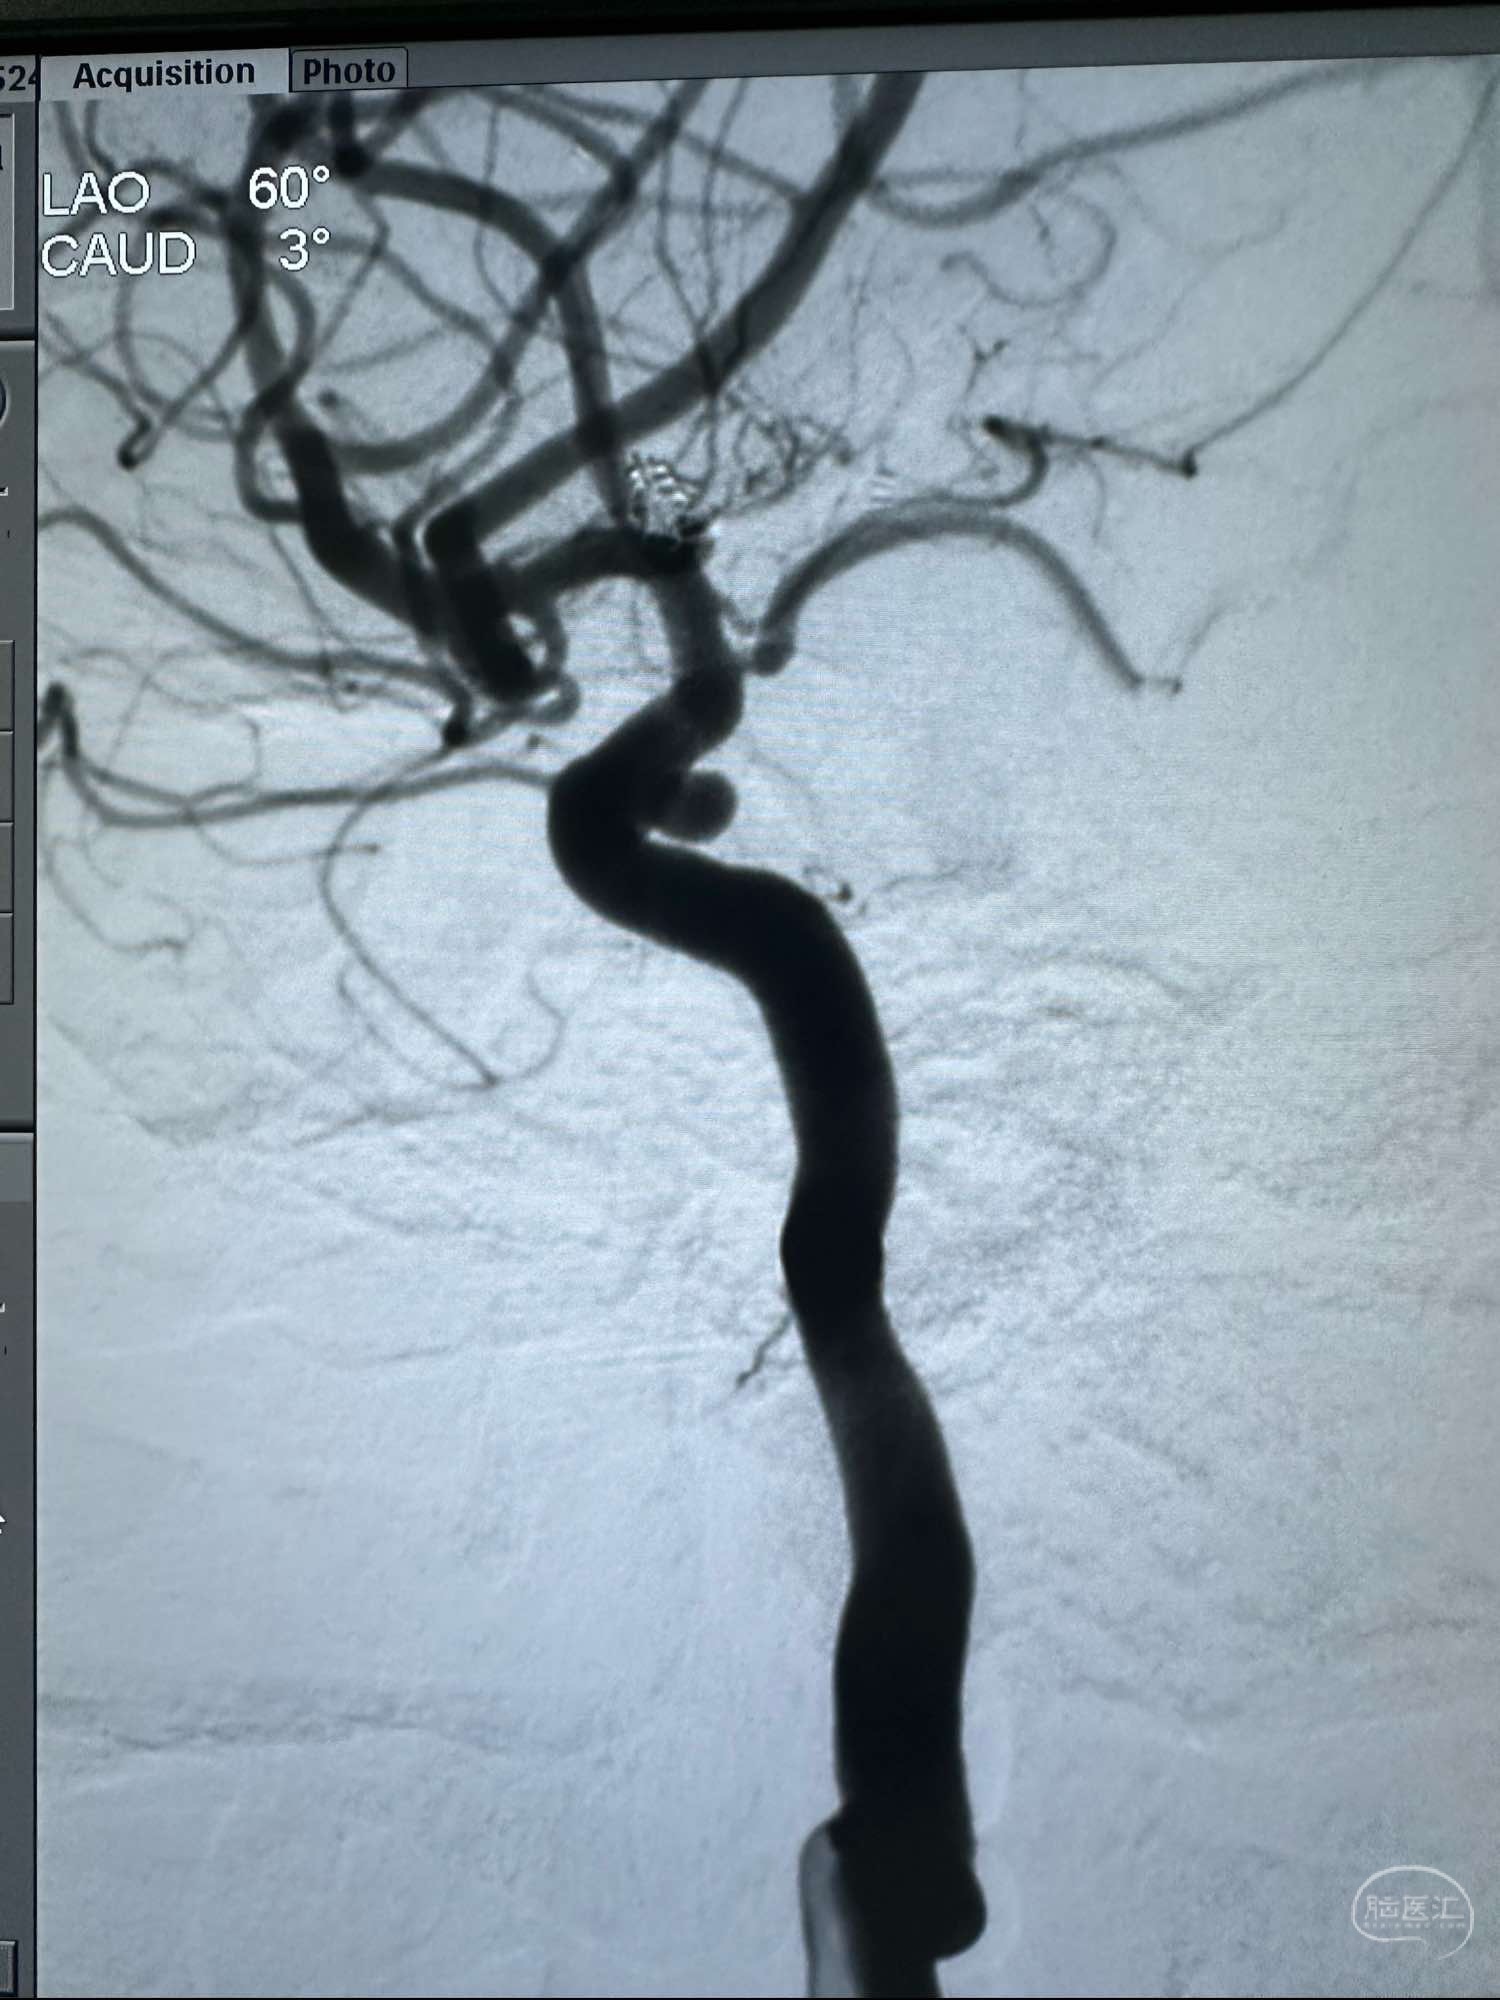

侧位

侧位